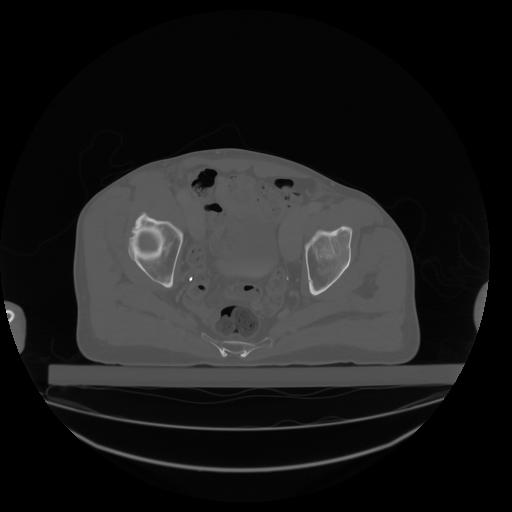

27 CUERPO,CE,Axial,3.0,CUERPO,,